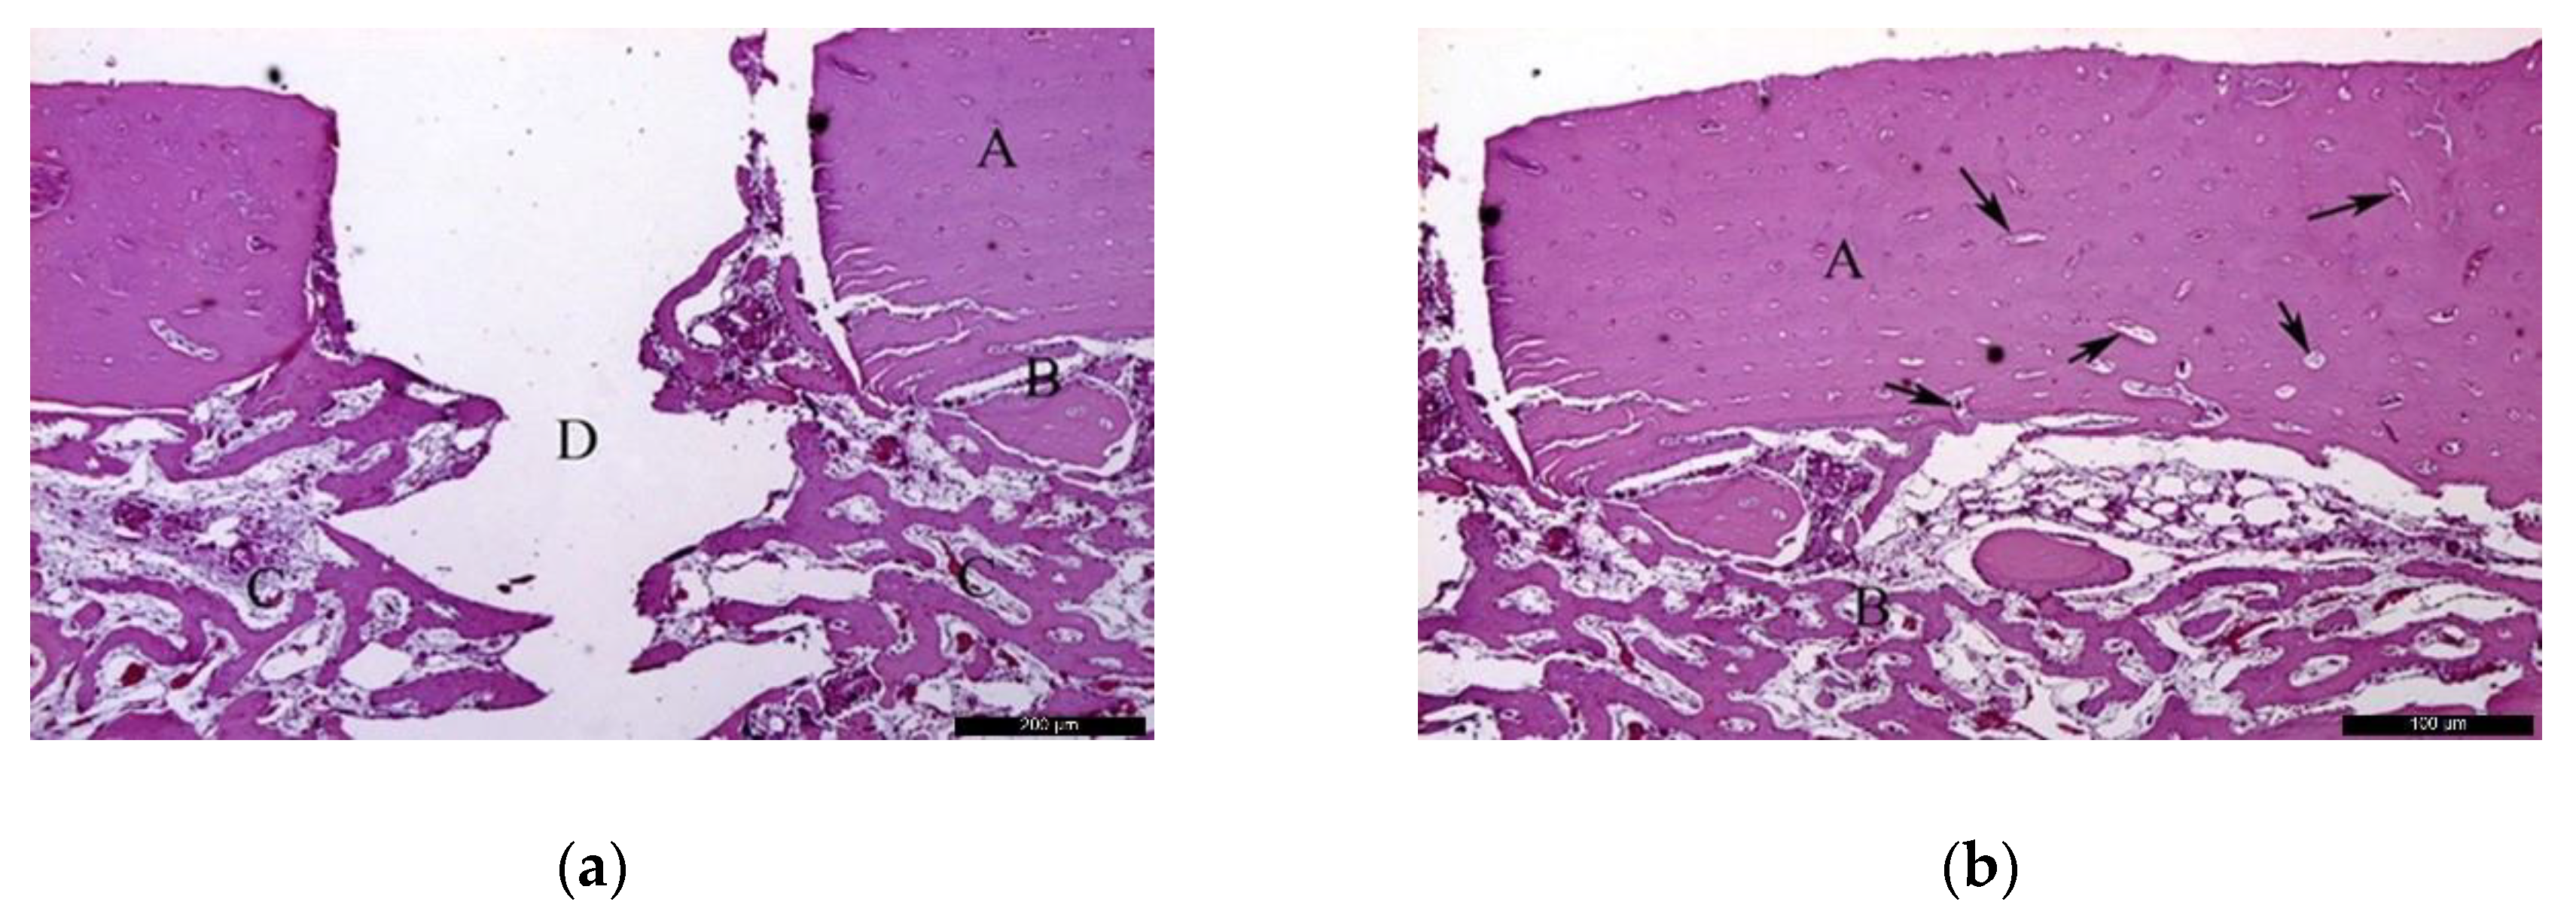

- Biomaterial group

In the BG, after 30 healing days (Figure 5a), it was possible to observe the biomaterial (A) in close contact with the newly formed bone (B), and the residual recipient site (C). In the surrounding areas of the neoformed bone, it was possible to identify a high number of lining cells compatible with osteoblasts (blue arrows) suggesting a phase of matrix synthesis. At higher magnification (Figure 5b), the contiguous contact between the biomaterial (A) and the neoformed bone (B) was appreciated. Lining osteoblast cells were identified in the periphery of the newly formed bone (blue arrows).

Figure 5.

Histological analysis of the biomaterial group (BG) at 30 days. (a) Biomaterial (A) in close contact with the newly formed bone (B), and the residual recipient site (C); osteoblast-like lining cells are indicated with blue arrows. Hematoxylin and eosin stain at a magnification 40×; (b) Biomaterial (A), newly formed bone (B), and lining osteoblast cells in the periphery of the newly formed bone (blue arrows). Hematoxylin and eosin stain at a magnification 125×.

In the BG, after 60 post-operative days (Figure 6a), the biomaterial (A) was enwrapped by neoformed bone (B). In the inner part of the biomaterial, it was possible to observe islands of newly formed bone, highlighting the osteoconductivity capability of the bone substitute. At the same time, areas of resorption associated with volume loss were noticed, indicating high solubility of the biomaterial. At higher magnification (Figure 6b), it was possible to observe the bone substitute (A) on the recipient bed (B), and neoformed bone tissue (C).

Figure 6.

Histological analysis of the BG at 60 days. (a) Biomaterial (A) enwrapped by newly formed bone (B). Hematoxylin and eosin stain at a magnification 40×; (b) Biomaterial (A) on the recipient bed (B), and newly formed bone (C). Hematoxylin and eosin stain at a magnification 125×.